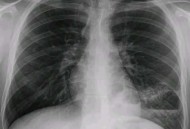

网络资讯用AI问诊双肺现空洞,双肺空洞病变大家好,今天小编关注到一个比较有意思的话题,就是关于用AI问诊双肺现空洞的问题,于是小编就整理了1个相关介绍用AI问诊双肺现空洞的解答,让我们一起看看吧。200...发布时间:2025年09月23日立即查看